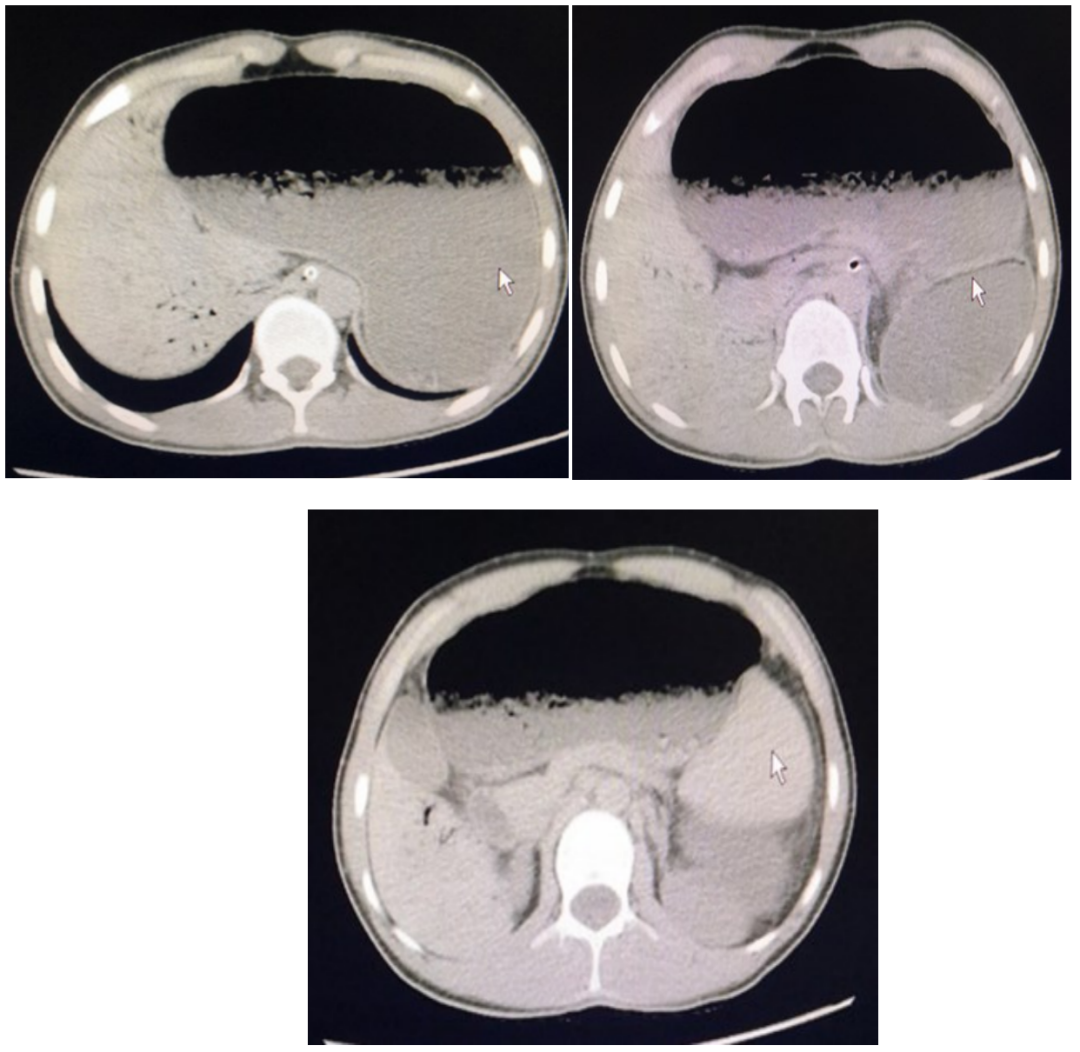

患者,男性,15岁,学生,以“恶心、呕吐、腹胀1天”为主诉入院。患者1天前进食过饱后出现恶心、呕吐、腹胀,同时伴有排气减少、纳差,大便量少 ,无腹痛、发热、反酸、烧心等不适,小便无异常,自行停止进食水后症状稍好转。发病以来,患者神志清,精神差,未进食,体重无明显下降。既往体健,无高血压、糖尿病、冠状动脉粥样硬化性心脏病、手术病史。生命体征平稳,神志清,精神欠佳,双肺呼吸音清,未闻及干湿性啰音,心律齐,心脏各瓣膜听诊区未闻及病理性杂音,腹软,膨隆,上腹部为主,可闻及震水音,肝脾肋下未触及,无压痛及反跳痛,肠鸣音弱,双下肢无水肿。入院后实验室检查:血常规、肝功能、肾功能、电解质、凝血、免疫、淀粉酶、脂肪酶、血栓两项均无异常。青少年男性,恶心、呕吐、腹胀、排气排便减少,首先考虑肠梗阻。肠梗阻临床上一般分为血运性、动力性、机械性,但该患者无手术史、近期无消瘦、既往无心房颤动、冠状动脉粥样硬化性心脏病,都不太支持。入院后给以禁食、抑制胃酸分泌、补液等对症支持诊疗,行上腹部CT检查,结果如下:结合患者病史以及CT结果,聪明的读者有想到是什么疾病吗?

小提示:仔细分析CT结果哦~